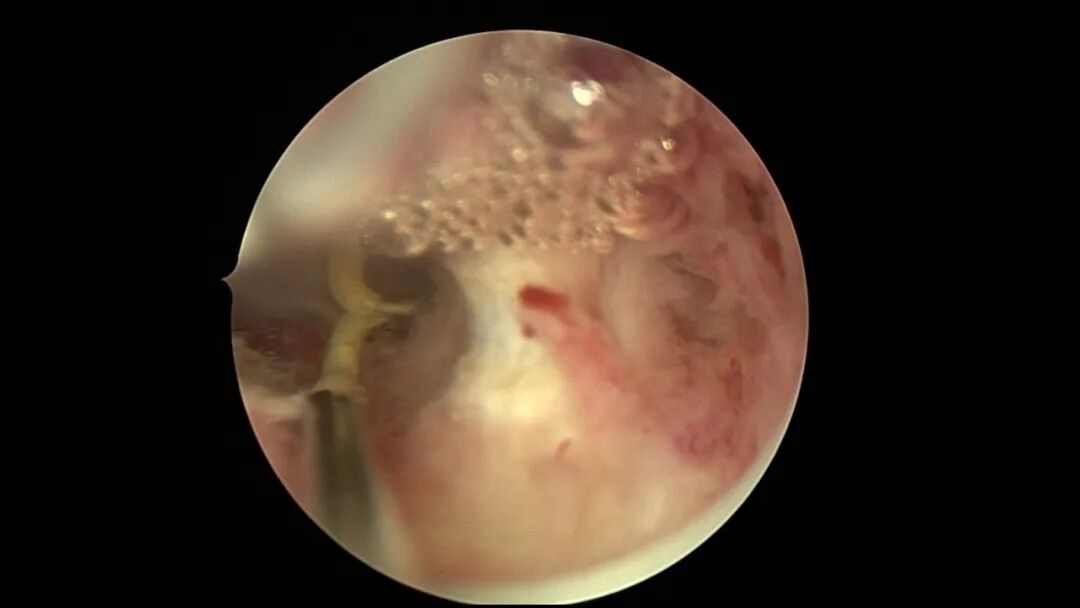

第三次宫腔镜:2021年9月,停经1+月,排除带环受孕,门诊B超提示宫腔粘连,节育环嵌顿。宫腔镜探查见γ型环嵌顿,宫腔广泛粘连,异物钳取环,环变形。单极电针分粘,恢复宫腔形态,显露双侧输卵管开口,右侧输卵管开口周围及宫底部分内膜正常,左侧宫角周围内膜薄,宫腔中部前后壁粘连创面集中,宫腔灌注生长激素。